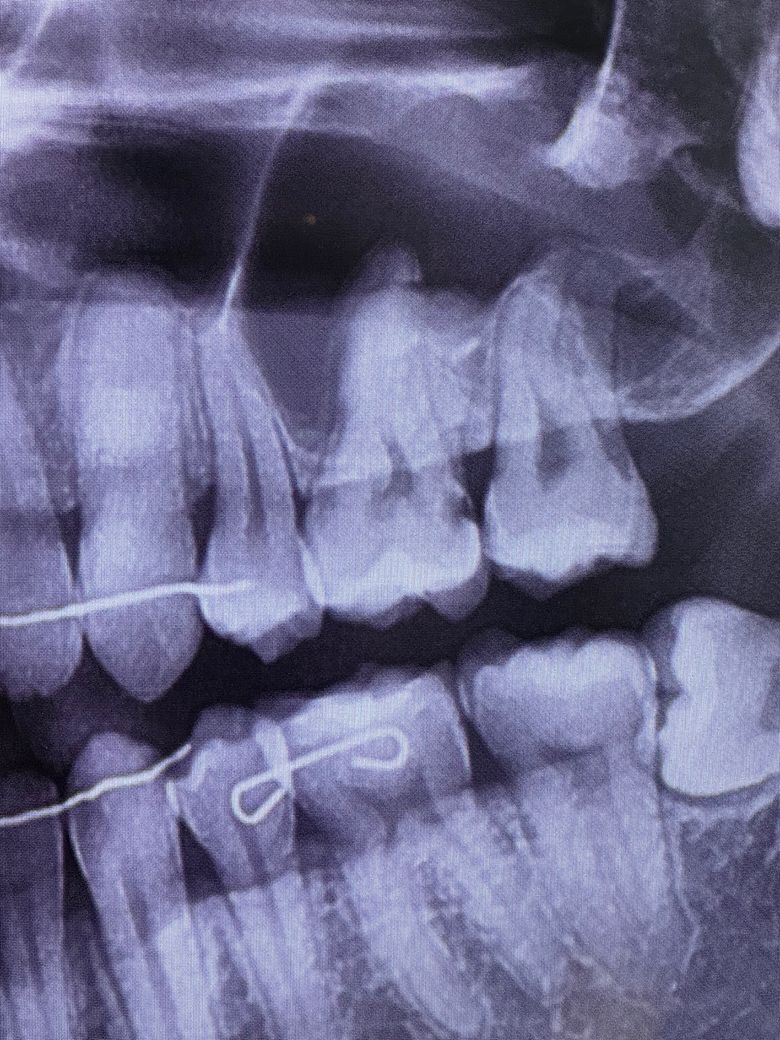

어금니 충치 신경치료까지 해야될까요?

위쪽 어금니 충치치료를 하려하는데 한 곳은 신경치료까지 해야될수도 있다 그러고 다른 한 곳은 일단 인레이만 하자는데 어떻게 보시나요? 충치부분 통증은 없어요

충치가 신경이랑 굉장히 가깝게 진행이 된거 같습니다 신경치료를 해야될 가능성이 높아 보입니다.

엑스레이사진상 일단은 신경까지 충치가 도달하진 않은것으로 보여 인레이를 목표로 하지만 충치를 실제로 제거하다보면 신경이 노출될 수도 있고 그러면 신경치료해야합니다